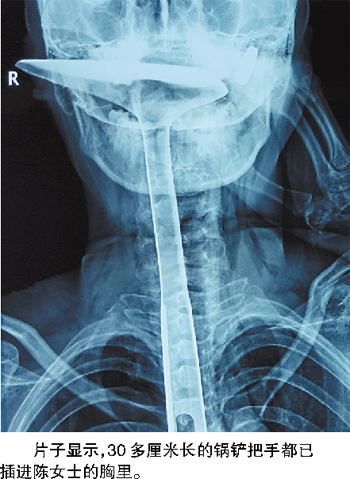

陈女士被紧急送到医院,当晚又被转送到康华医院。在医院拍的片子显示,30多厘米长的锅铲把手都已插进陈女士的胸里,情况非常危急。记者从医生手机里保存的照片上看到,当时陈女士的嘴巴张着,只有锅铲的前端还露在嘴巴外面,她的左手扶着锅铲,锅铲上和手上都是血。